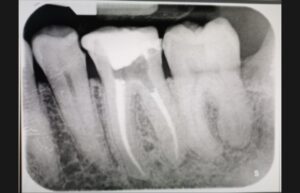

Caso clinico pulpite

questo è un caso di pulpite, denti multiradicolari devitalizzati nel nostro reparto specializzato.